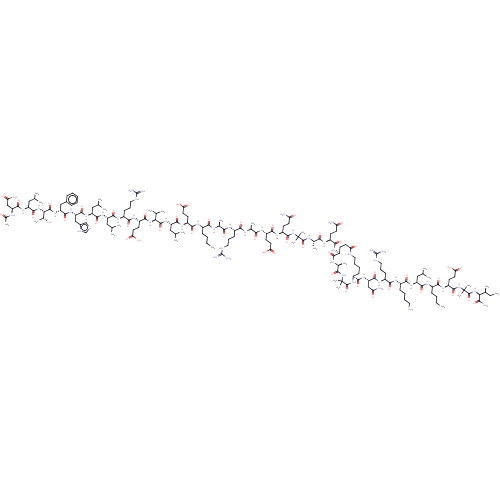

TargetCorticotropin-releasing factor receptor 1(Homo sapiens (Human))

Dupont Pharmaceuticals

Curated by ChEMBL

Dupont Pharmaceuticals

Curated by ChEMBL

Affinity DataEC50: 3.5nMAssay Description:Activity of peptidic agonists on corticotropin releasing factor receptor receptor using agonist-stimulated adenylate cyclase assayMore data for this Ligand-Target Pair